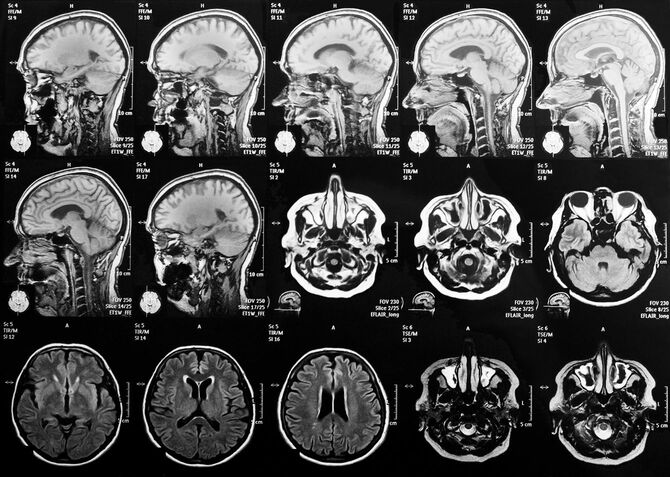

「7月頃母は、『頭がボーッとする。なんだか自分がおかしい』と訝しんでいて、『心配だから、一度病院で診てもらおう』と言ったらすんなり受診することになりました。本人も不安だったんだと思います。脳神経外科でMRIを撮ってもらった結果、脳の萎縮がみられることと、日常生活の状態を話したうえで、『アルツハイマー型認知症』の診断を受けました」